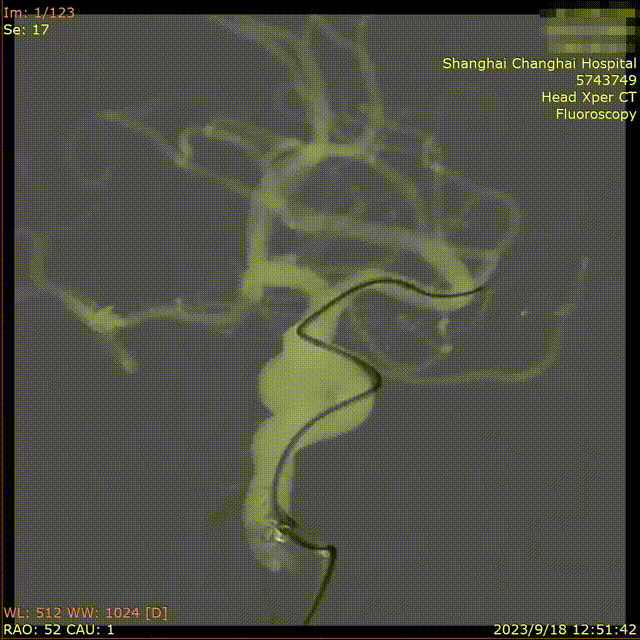

术前造影

患者全麻后,右侧股动脉 Seldinger法穿刺,置6F动脉鞘, 6F导引导管在导丝导引下超选到左侧颈内动脉破裂孔段,选择最佳工作角度,路图下用微导丝(Platinum.014in)辅助微导管(Prowler select Plus)超选至左侧M1。

路图下用微导丝(Platinum.014in)辅助微导管(Echelon-10)超选至动脉瘤瘤体内。